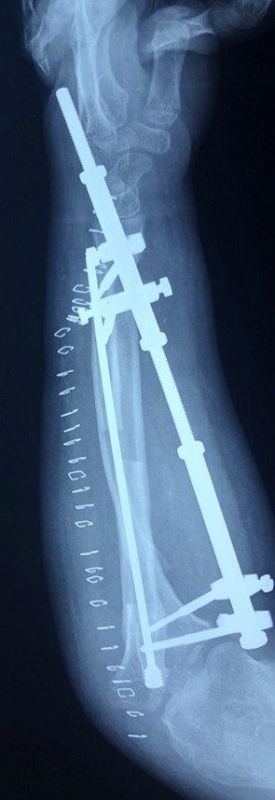

Дети из ЛНР проходят бесплатное лечение в НМИЦ травматологии и ортопедии им. Н.Н. Приорова Минздрава РоссииДвум маленьким пациентам - родным братьям 9 и 11 лет провели сложную хирургическую операцию по программе государственных гарантий бесплатного...